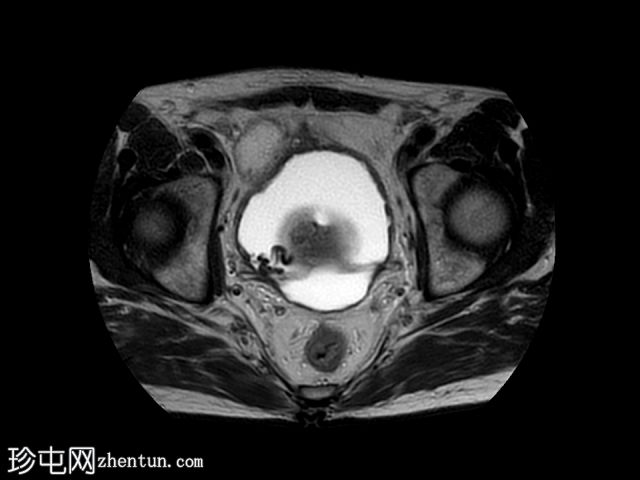

轴位

T2加权像

在T1和T2加权像上,于膀胱底部及右下外侧面偶然发现一处呈蛇形缠绕状的低信号区。动态序列中可见快速对比增强,提示所有影像学表现均源于血管,信号缺失与动静脉畸形有关,该畸形至少由膀胱下动脉供血,并由同侧局部扩张的静脉回流。

这些影像学表现符合局限性动静脉畸形,这种情况极为罕见。通常情况下,该畸形伴有肉眼血尿,但本例患者未出现此症状。通常情况下,该畸形由髂内动脉的多条供血动脉供血,血管造影被认为是确诊的金标准。